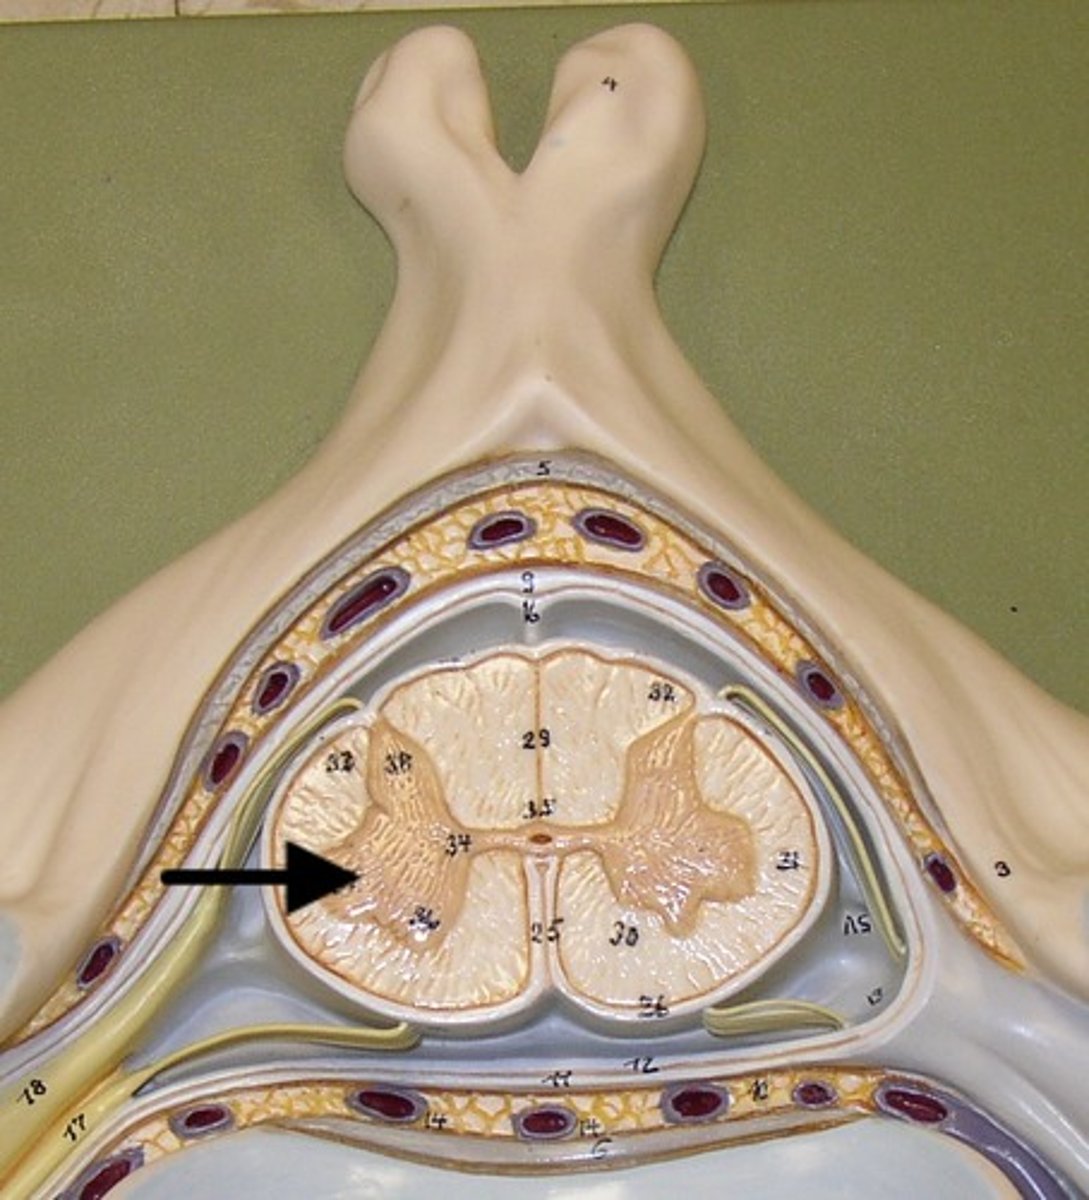

Gray Matter

1

Posterior Horn

2

Anterior Horn

3

Lateral Horn

4

Gray Commissure

6

Central Canal

5

White Matter

7

Posterior funiculus

8

Anterior Funiculus

9

Lateral Funiculus

10

Posterior median sulcus

Anterior Median Fissure

Dura mater

arachnoid mater

pia mater

epidural space

subdural space

subarachnoid space